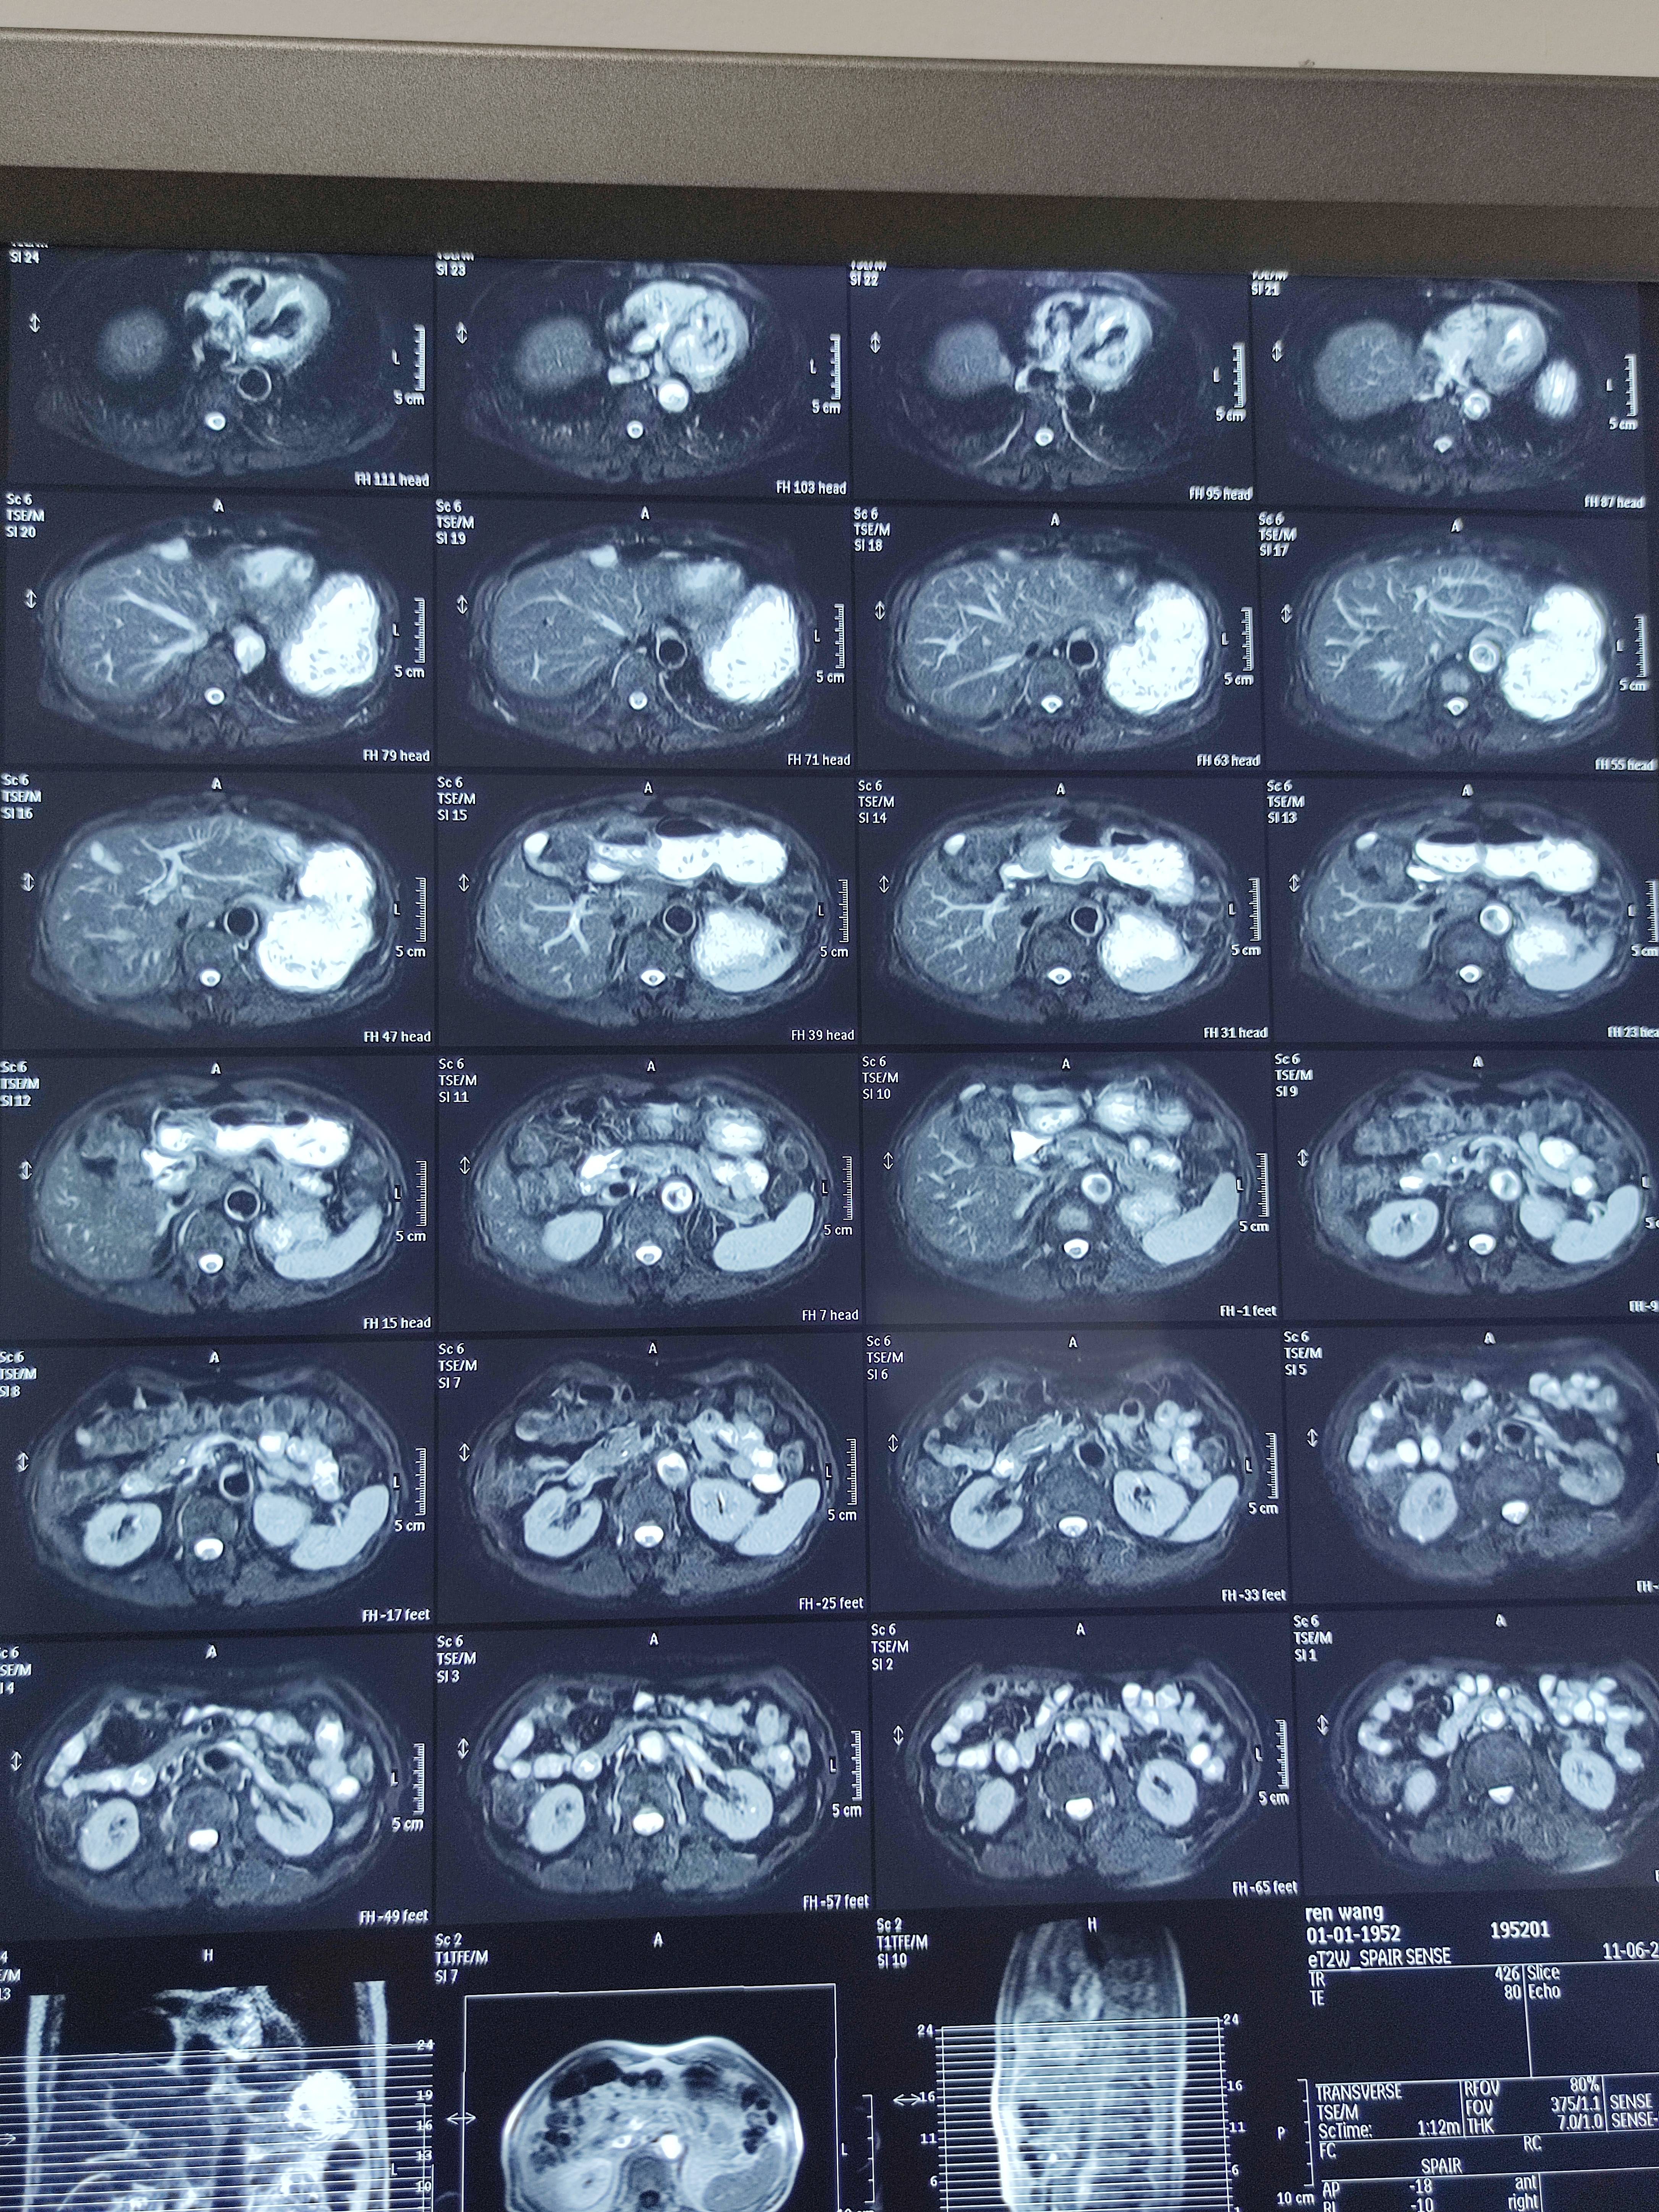

四月份癌胚抗原还是5.6,这个月到8了,持续升高。做了核磁增强,左侧桥小脑角哪有个地方不确定。肝脏核磁平扫弥散有两个点状高信号,转移也排不了,胃肠镜正常,左颈部有个变圆的淋巴结,保险点是不该加个化疗药了?咨询了陈波主任,等结果的吧!图片